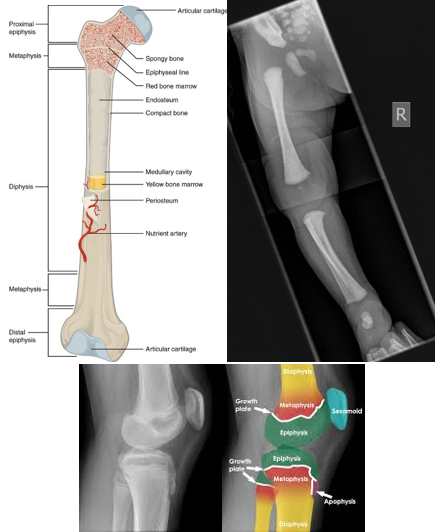

Pediatric Bone Anatomy

Infant skeleton is not fully ossified at birth.

Thick, strong periosteum—outermost lining of the bone—(better shock absorber!)

Pediatric bones can bend up to ~45 degrees before breaking.

Due to this, sometimes children can have more of an incomplete fracture than one an adult would have.

Bone ossification (cartilage to bone) is complete by adolescence.

The growth plate at the end of long bones is composed of the epiphysis and physis (epiphyseal growth plate).

The growth plate is the most vulnerable part of the bone.

Bone growth occurs here.

**The growth plate must be protected at all costs! If it is damaged, it can interrupt blood supply and cause growth failure**

When describing a fracture as a nurse:

Name the bone affected.

Note if it is open (bone breaks through skin) or closed (skin is intact, the bone did not break through).

Note if it is distal or proximal.

Specify the part of the bone injured: epiphysis, metaphysis, diaphysis, or physis (Salter-Harris Classification)

Note if it is displaced or nondisplaced.

Displaced = ends do not line up; the patient tends to have a pretty significant amount muscle of spasms and their pain is worse.

Describe the type: transverse, oblique, spiral, or depressed.